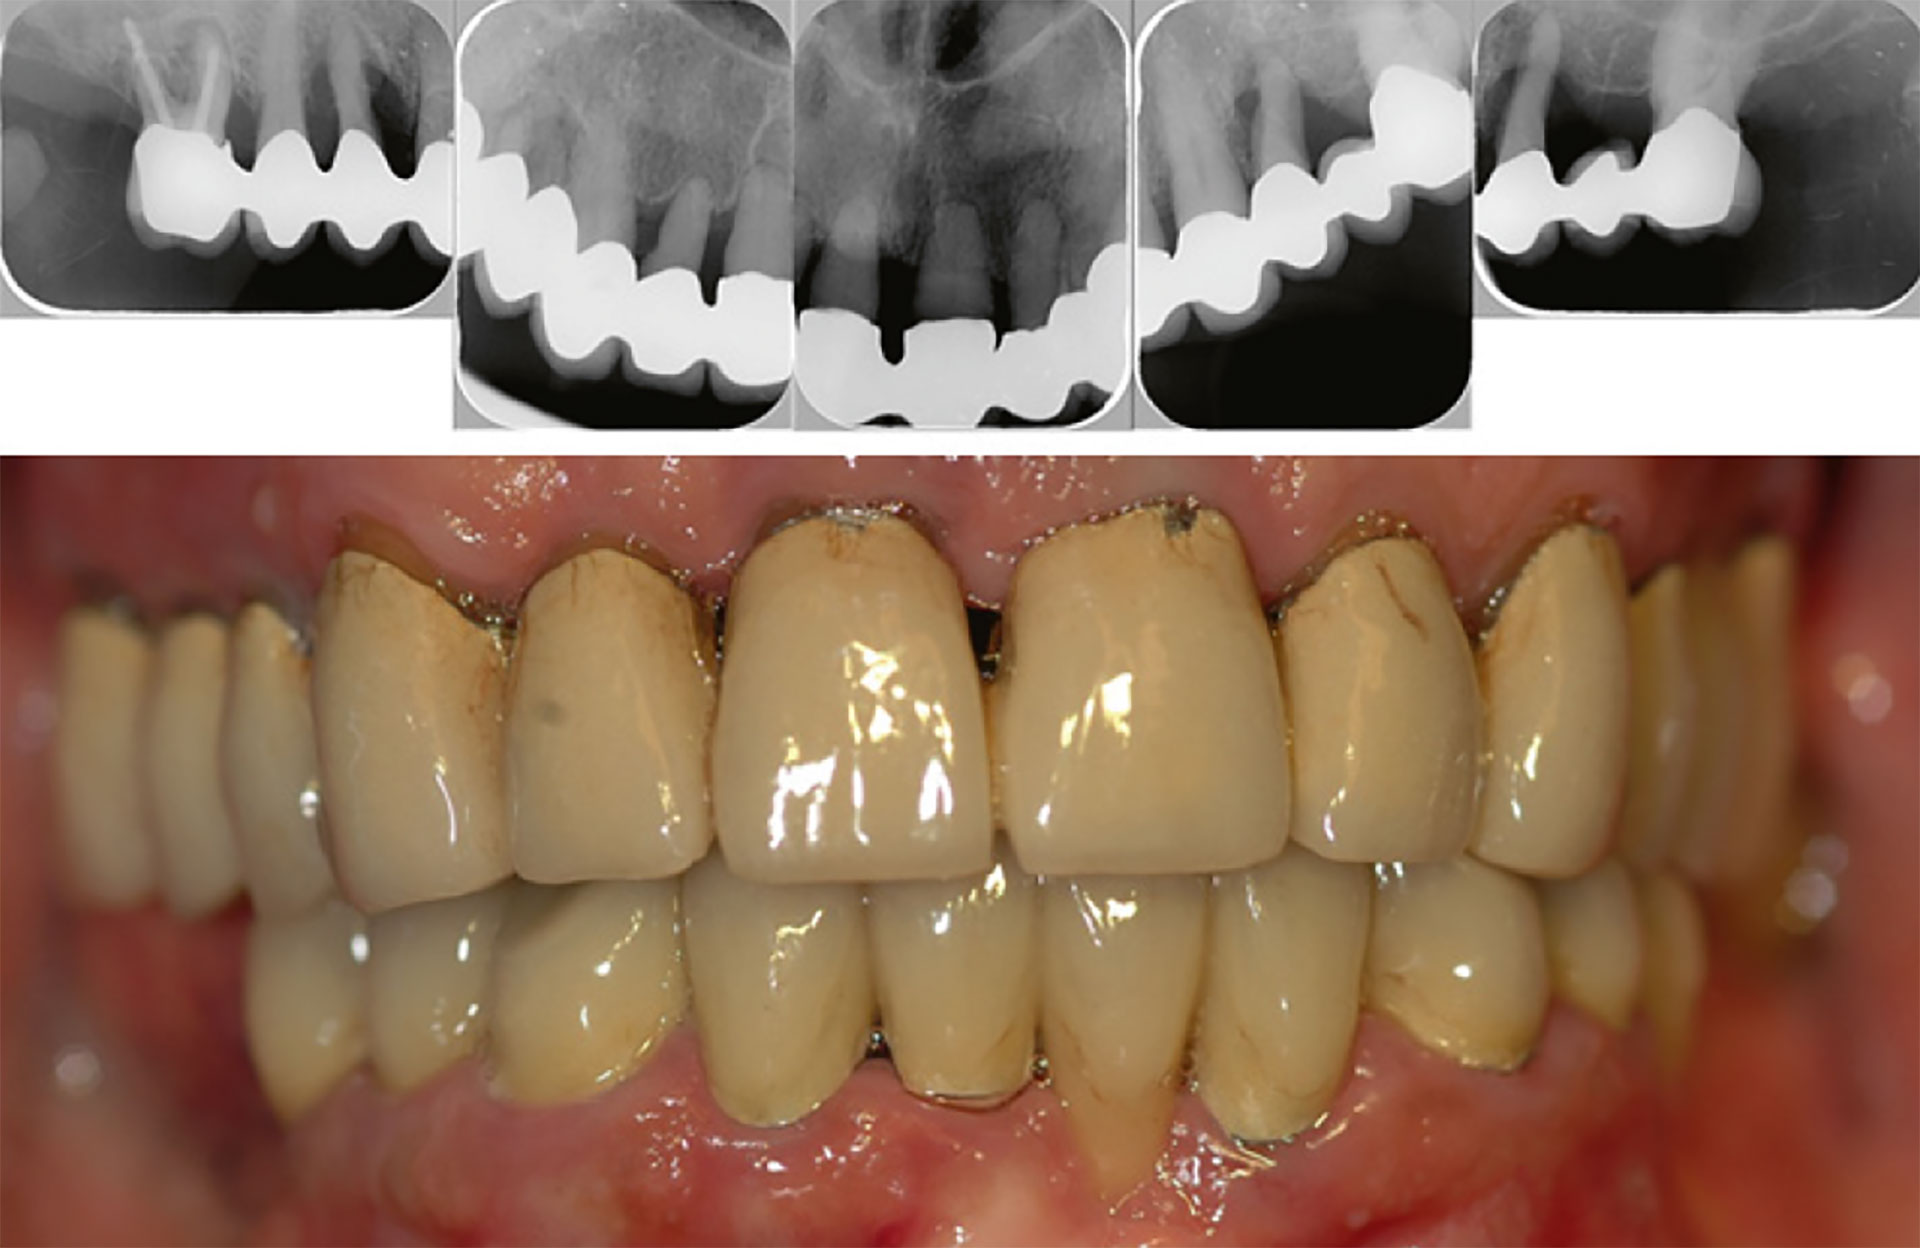

Bro i overkjeven sementert i 1993. Radiologisk bilde fra 2012 og klinisk bilde fra 2025. Foto: Øystein Fardal.